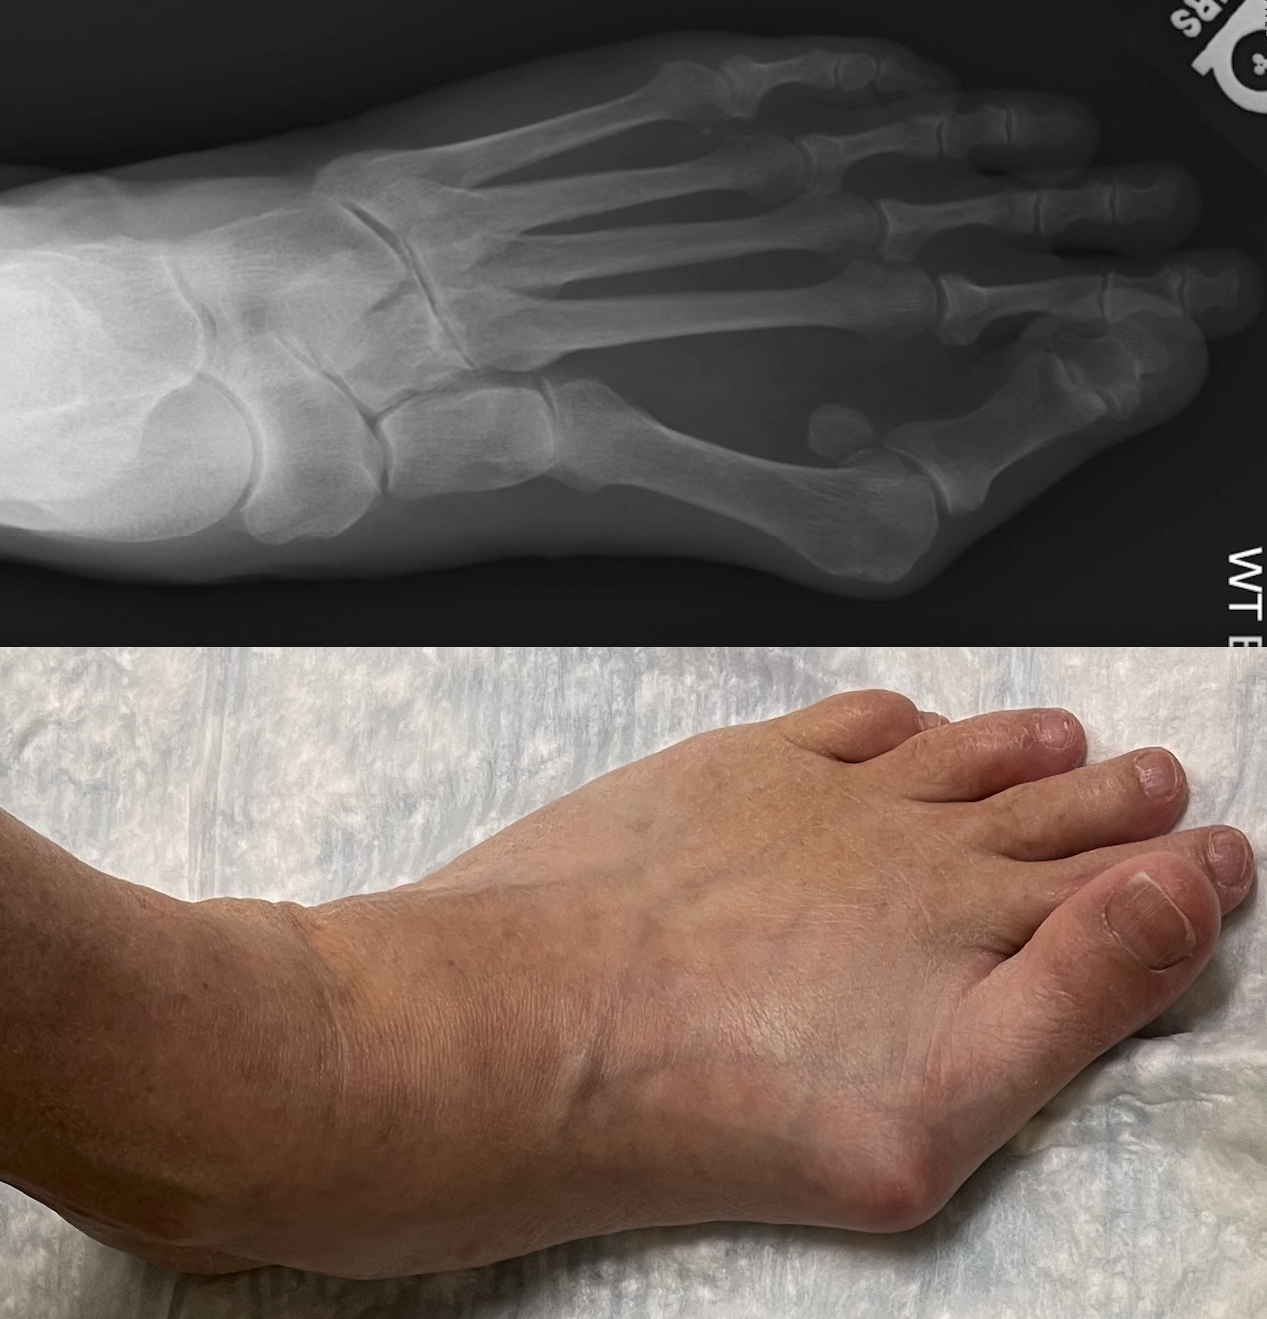

Pre-operation images of a bunion Images: UT Southwestern

Bunions form on the base of the big toe when the long metatarsal bone shifts toward the inside of the foot and its phalanx bones angle toward the second toe. As the soft tissue of the foot rubs up against shoes, pain results.